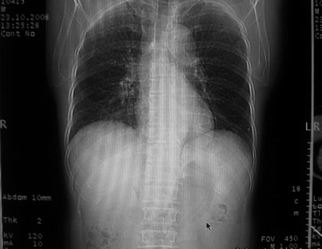

男,62岁,咳血两天。无其他不适。

右肺上叶浅淡密度增高影,考虑炎性病变

片状磨玻璃影,考虑肺泡出血可能性大,其他不排除,建议hrct

右上磨玻璃样密度影,考虑就是个肺泡出血,别的没有

病灶呈“磨玻璃影”,较薄,周围无卫星灶,很难一口说是肺结核,建议积极治疗后,短期复查!(支持考虑:肺泡出血!)

右肺上叶可见多发磨玻璃状影,符合肺泡内出血表现,严格意义上讲应该是肺泡内积血。引起出血的原因很多,不一定非得结核所致。